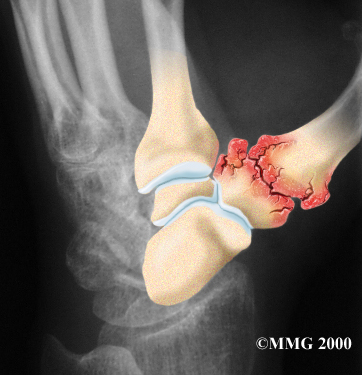

Arthritis is a condition in which a joint becomes inflamed (red, swollen, hot, and painful). Degenerative arthritis is a condition in which a joint wears out, usually slowly over a period of many years. Doctors sometimes also describe this same condition as degenerative arthrosis. It is also called osteoarthritis.

Degenerative Arthritis

Injury to a joint, such as a bad sprain or fracture, can cause damage to the articular cartilage. An injury to the CMC joint of the thumb, even if it does not injure the articular cartilage directly, can alter how the joint works. After a fracture of the thumb metacarpal, the bone fragments may heal in slightly different positions. The joints may then line up differently. This is also true when the ligaments around the CMC joint are damaged by a sprain. When an injury results in a change in the way the joint moves, the injury may increase the forces on the articular cartilage surfaces. This is similar to any mechanical device or machinery. If the mechanism is out of balance, it tends to wear out faster.

Over many years this imbalance in the joint mechanics can lead to damage on the articular surface. Since articular cartilage cannot heal itself very well, the damage adds up. Eventually, the joint is no longer able to compensate for the increasing damage, and it begins to hurt. Damage has occurred well before the pain begins.